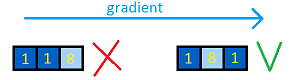

5. Все оставшиеся воксели считаются границами. На основании значения градиента, порога кальция (который доступен не сразу) и близости к “вертикальному” центру, каждой точке присваивается определенная стоимость (чем ярче воксель, тем выше его приоритет при поиске пути):

В таком виде границы сосуда уже практически однозначно определены.

6, 7. Чтобы построить границы воспользуемся поиском пути. В качестве начальной и конечной берутся ближайшие крайние точки с наименьшей стоимостью. Для поиска пути используется обычный поиск в ширину, который выбирает граничные точки с наименьшей стоимостью. Также доступны прыжки, но цена их высока. Верхняя и нижняя границы сосуда ищутся раздельно, и после к ним применяется сглаживание: